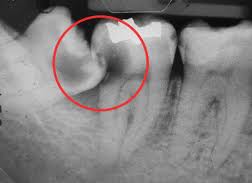

写真左下の親知らずが痛くなり抜歯しました。その後歯茎を除去して虫歯を露出させる処置を二回ほどしています。

レントゲンでは小さいですが、こう言う虫歯が一番怖いのです。

治療の成功率は極めて悪くすぐ再発しやすいのです。